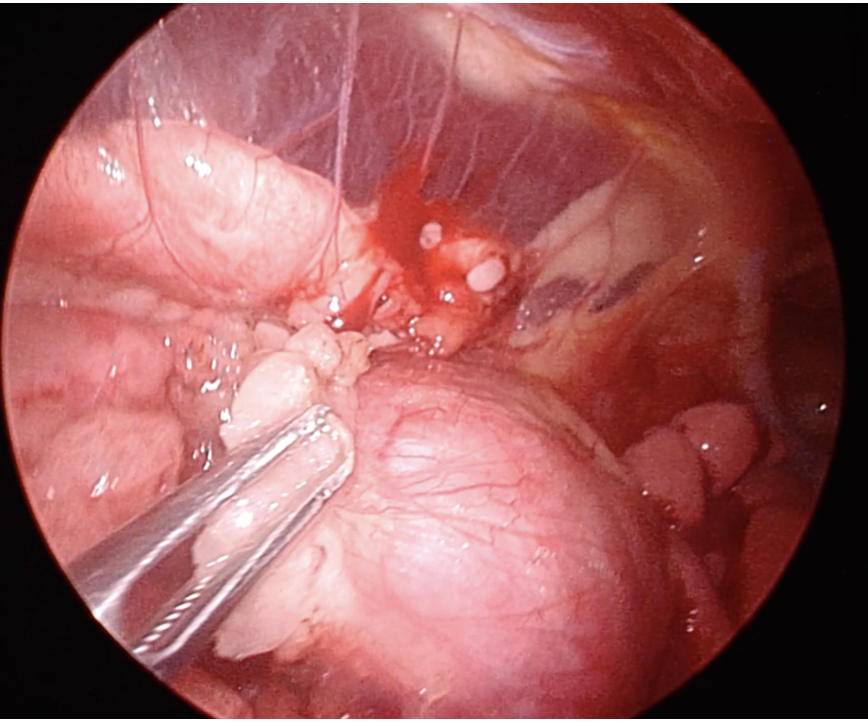

そこで今回飼い主さんの同意もあり、体格が大きい子(32kg)ということもあったため、体への負担が少ない(低侵襲手術)胸腔鏡手術での腫瘍摘出を実施いたしました。

胸腔鏡手術は開胸手術よりもさらにできる施設は少なくなります。大学病院と一部の専門病院を除くと設備的に実施することが困難で、特殊な麻酔の技術も必要となるため、ほとんど実施されておりません。当院にはトレーニングを受けた獣医師と優秀な麻酔科があるため、胸腔鏡実施が可能です。

今回は2時間程度の手術で、無事に腫瘍は摘出され、本人の状態もとても良かったため、翌日に帰宅となりました。術後のX線で腫瘍がきれいになくなっているのが分かると思います。胸腺腫は摘出が完全に実施されると比較的予後が良いと言われています。今回の手術でわんちゃんが元気で長生きできることを願っております